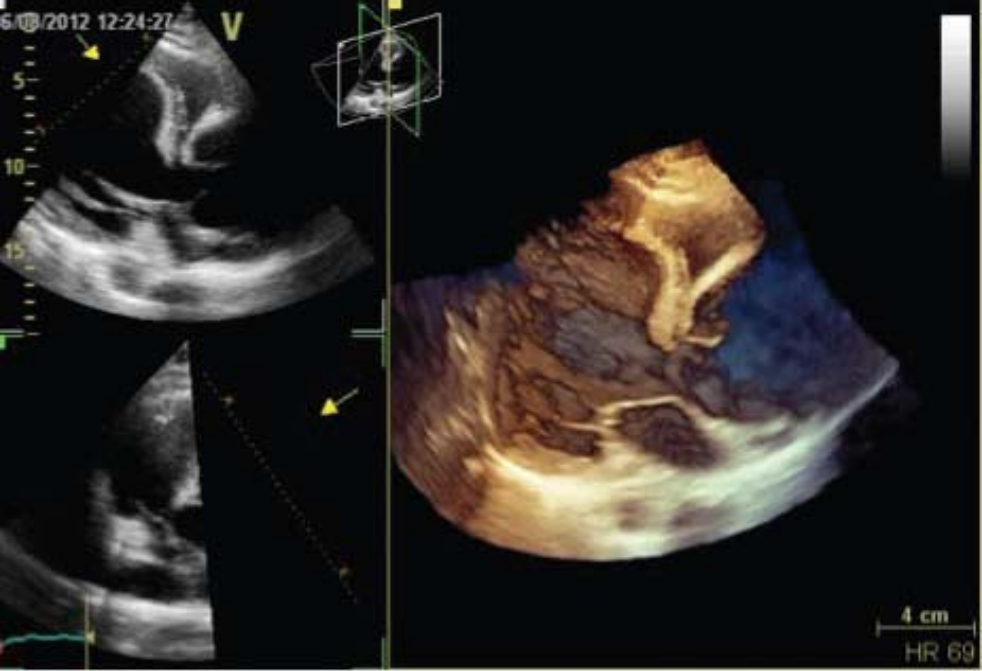

The TTE, using both multi planar and 3D acquisition (Figure 2a),

Transthoracic echocardiography with 3D acquisition of  aortic valve.

Figure 2a: Transthoracic echocardiography with 3D acquisition of aortic valve.

showed a severe aortic insufficiency [tricuspid valve; vena contracta = 8.3 mm, pressure half-time = 234 ms (Figure 2b),

secondary to a large ascending aortic aneurysm (Figure 2d),

Transthoracic echocardiography – suprasternal view,  showing a dilation only of the ascending aorta.

Figure 2d: Transthoracic echocardiography – suprasternal view, showing a dilation only of the ascending aorta.

with the following 2D measures: aortic ring = 4.1 cm, Valsalva sinuses = 5.18 cm, sino-tubular junction = 7.1 cm and ascending aorta = 8.7 cm. The left ventricle was enlarged, with ejection fraction (calculated by Simpson’s method and using 3D software) of 41% and global longitudinal strain of -14.4% (Figure 3).